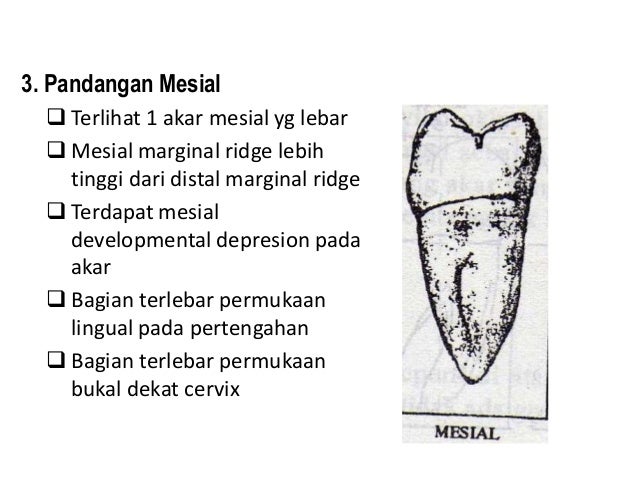

2. dental anatomi gigi permanen ..

2. dental anatomi gigi permanen ..

10. morfologi gigi permanent rahang bawah

10. morfologi gigi permanent rahang bawah

9. morfologi gigi permanent rahang atas

9. morfologi gigi permanent rahang atas

Gigi Molar Rahang Bawah - [PPT Powerpoint]

Gigi Molar Rahang Bawah - [PPT Powerpoint]

Gambaran Umum Molar Kedua Mandibula, Gambaran Umum Molar Ketiga Mandibula, Aspek Bukal, Aspek Lingual, Aspek Proksimal, Aspek Oklusel, Bagian-Bagian Occlusal Table | DuniaKuMu

Gambaran Umum Molar Kedua Mandibula, Gambaran Umum Molar Ketiga Mandibula, Aspek Bukal, Aspek Lingual, Aspek Proksimal, Aspek Oklusel, Bagian-Bagian Occlusal Table | DuniaKuMu